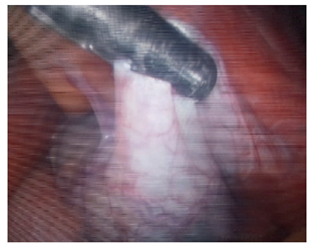

En vista de la agudización de los síntomas, se ordenó una laparotomía exploratoria. Durante la intervención quirúrgica por vía mediana subxifoidea se halló vólvulo de la vesícula biliar con ausencia del mesenterio de fijación al lecho hepático y amplio en el conducto cístico, colecistitis isquémica (infarto vesicular) (figura 3). Se procedió a corregir el vólvulo y a la disección del triángulo de Calot, identificándose vía biliar de diámetros normales (figura 4). Se ligaron el conducto cístico y la arteria cística. Luego de la extirpación de la vesícula biliar flotante del lecho hepático, se observó conducto cístico normal (figura 4). Posteriormente, el abdomen se cerró por planos. El acto quirúrgico transcurrió sin complicaciones.

Durante la hospitalización se practicó colangiorresonancia magnética, en la que se confirmó vólvulo de la vesícula biliar y disminución del flujo sanguíneo en su pared. Por el empeoramiento de su dolor abdominal, 10/10 en la escala análoga, se ordenó colecistectomía urgente por laparoscopia, la cual fue convertida por malrotación intestinal incompleta (ciego y apéndice en el hipocondrio izquierdo de tipo III de Stringer, plastrón vesicular y distorsión de la anatomía) (figuras 6 a 7). Se corrigió el vólvulo y se hizo colecistectomía. La evolución posoperatoria fue satisfactoria.